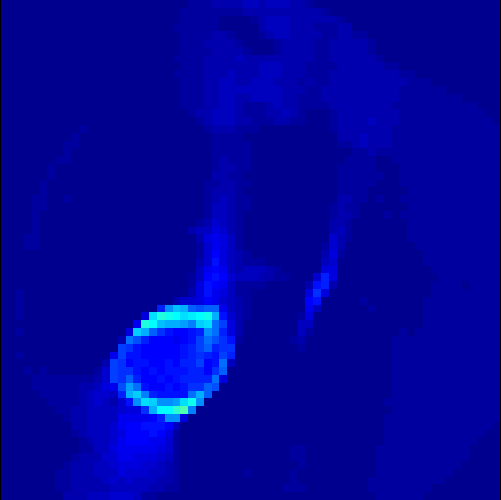

5.2 Monte Carlo Simulation

In order to test the behaviour of the proposed method in a more realistic, random-based test case, we performed a Monte Carlo simulation for dynamic SPECT imaging. First, we created a simple image phantom consisting of an outer and two inner circles which represents the structure of the region of interest (see figure 8(a)). Within those regions we assumed concentration curves over a time period of 90 time steps as displayed in figure 8(b). Based on the tracer intensity in an image frame at each time step, we created a variable number of random decay events (where the number is proportional to the average concentration in one pixel in the whole image frame per time step) with a probability proportional to the concentration in every subregion. They are detected by a virtual double head gamma camera rotating around the patient by 46 degrees per time step, which consists of 374 detector bins. Every simulated decay event is projected onto the scanner and counted by the corresponding detector bin.

In two different tests we fixed the number of events counted by the detector equal to (resp. ) times the average concentration in one pixel. The resulting sinogram images of the accumulated counts in each bin are shown in figure 9.

Based on the sinogram data we applied the proposed algorithm in order to reconstruct the original image sequence. The results for both test cases are shown in figure 10.

As one can see, the method is able to reconstruct the regions properly, even in case of a low count number. Within a number of iterations (average of 100 outer and 10000 inner iterations), the algorithm presents a reasonable reconstruction of the region of interest and the corresponding regional tracer concentration curves. Here, the parameters were not optimized as in the case of the synthesized data sets in the previous section, but kept fixed as , and . With futher optimized parameter values one could possibly provide even better results.